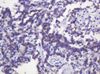

Applications IHC, WB

Recommended Dilution WB 1:2000, IHC 1:150